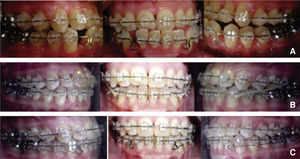

TREATMENT PROGRESSTreatment was begun with the placement of fixed appliances, 0.022” slot Roth system, in the upper arch. The Department of Periodontics conducted the scaling and root planning in the lower anterior area and subsequently, placed a free gingival graft. A month later fixed appliances were placed in the lower dental arch thus beginning the leveling and alignment with the corresponding archwires (Figure 6). Three segments were formed throughout this phase: one anterior segment and two posterior ones. After the segments were formed a single keyhole loop (SKL) archwire was placed in the lower arch maintaining a segment with ligature wire from lower first molar to canine on both sides. The archwire was activated in the following appointment with a Suzuki retroligature to begin space closure (Figure 7A).

Once the spaces were closed, the archwire was tied with ligature wire to form a block of teeth from second premolar to second premolar on the upper and lower arch and began to use 3.5oz, 5/16” class III elastics with a vertical vector (Figure 7B). Subsequently, the teeth # 11 and 21 were rebuilt with composite to recover their form and aesthetics as well as to maintain what had been achieved.

A panoramic radiograph was obtained to reposition the brackets accordingly. The brackets form teeth #42 and 35 were repositioned to achieve root parallelism.

After bracket repositioning, a space opened between the lower right lateral incisor and canine and reseated so the SKL archwire was placed again to close that space (Figure 7C); four months after, the fixed appliances were removed (Figure 8). As retention a circumferential retainer was placed in the upper arch, while a fixed retainer made with a 0.0175” braided wire and bonded with fluid resin was placed in the lower (Figure 9).